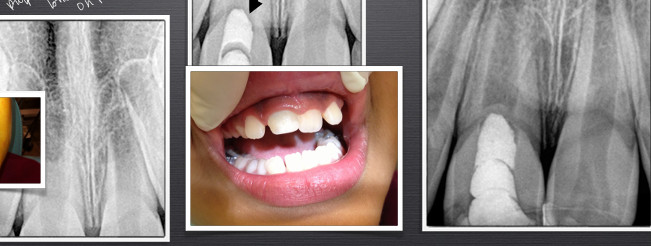

horizontal root fractures

-the more apical the fracture, the better the prognosis

-more apical means being more walled-off from the oral environment

-apical segment: blood supply maintained, never a problem

-coronal segment at risk: mobility, splint required for 4 weeks, RCT not needed (just observe)

-when coronal pulp necroses, see if you can reposition the segment and splint, or can do RCT on the coronal segment only

-if apical segment starts trouble, just do apicoectomy to treat

cervical root fracture

-outcome/treatment will depend on age of patient

-adult: don’t worry, can extract and implant

-child/adolescent: don’t want to extract- could compromise the alveolus; want to preserve the root, extract coronal segment, bury root under bone and use retention (essix retainer) for esthetics, when pt turns 18 could do implant then since the ridge will have been preserved